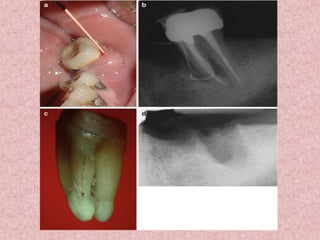

(a) Perforation of the pulpal floor of the mandibular first molar occurred in conjunction

with a search for root canal openings. There is also a file fragment in one of the mesial

canals.

(b) The perforation was immediately sealed with guttapercha.

(c) In a radiograph taken 1 month after treatment a slight radiolucency is seen at the

site of the perforation (arrow).

(d) Follow-up after 2 years showed normal periodontal conditions both clinically

and radiographically